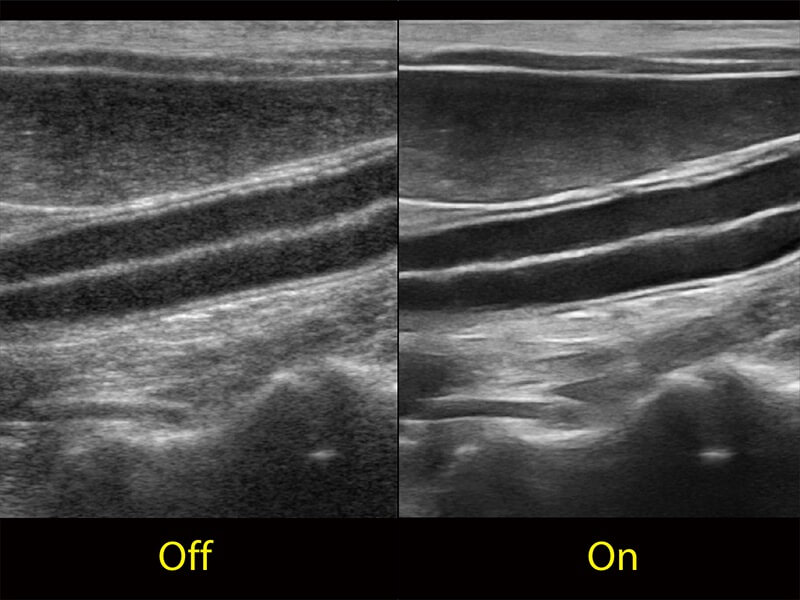

Przy pracach nad aparatem ProPet 60 uwzględniono najważniejsze preferencje i potrzeby weterynarzy, oferując finalnie przystępne cenowo i odpowiednio wyważone połączenie znakomitej precyzji klinicznej, zwiększonej wydajności i przemyślanego przebiegu pracy, niezastąpione w codziennej praktyce weterynaryjnej. Dzięki dostępowi do pełnej gamy głowic HD rozwiązanie to spełnia wszystkie potrzeby w zakresie obrazowania, umożliwiając wykonywanie badań jamy brzusznej, małych narządów, ortopedycznych, badań podczas rozrodu, a nawet badań serca i klatki piersiowej, a to wszystko przy doskonałym stosunku jakości do ceny.